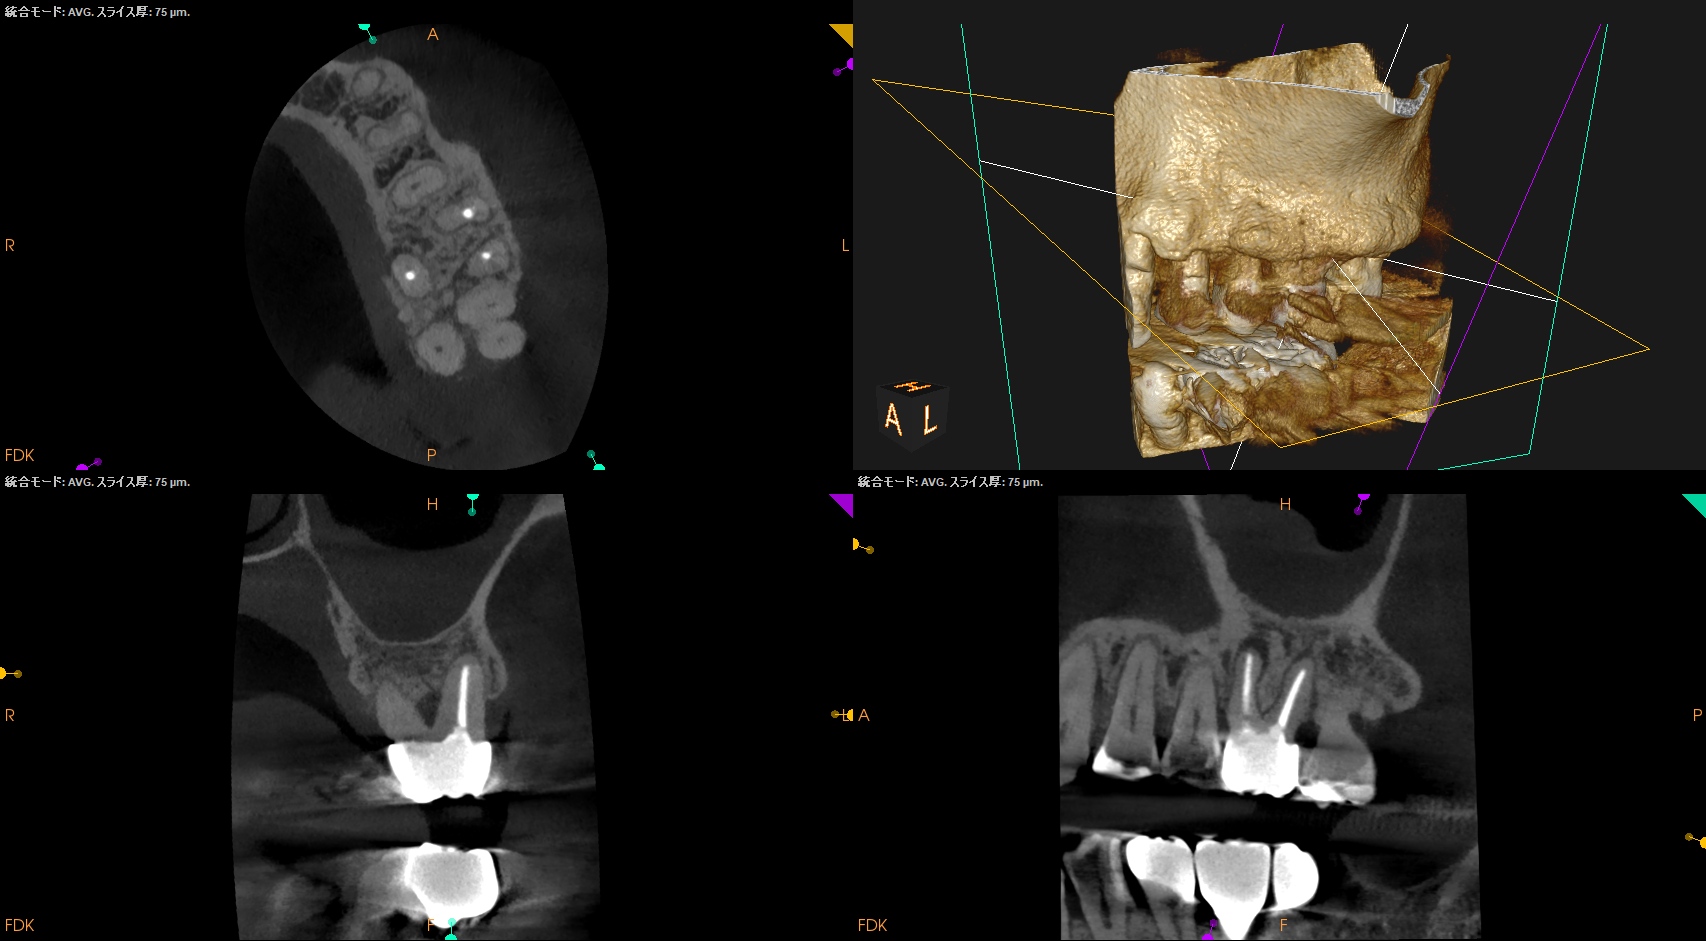

歯軸と並行になるようにCBCTのバーを動かした。

すると…

このような絵になる。

ここを、

こうすべきだろうか?

それともこのままで

いいだろうか?

中心に対して左右非対称に近くなることから私は修正しない道を選択した。

つまり、

この状態でOKと判断したのである。